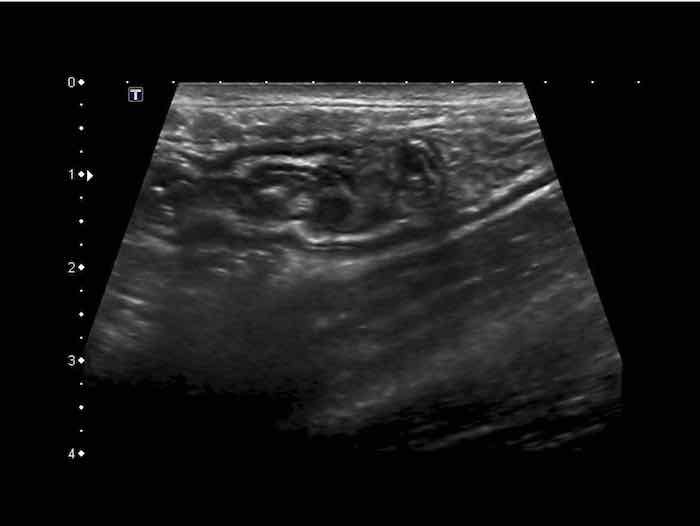

Đây là hình ảnh siêu âm của một trẻ 2 tuổi bị lồng ruột hồi manh tràng từng đợt, được khám trong khoảng thời gian giữa các cơn.

Hồi tràng với nhiều mảng Peyer sa vào manh tràng.

Hình ảnh siêu âm kinh điển của lồng ruột hồi-manh tràng ở hai trẻ khác nhau.

Trong cả hai trường hợp, đoạn hồi tràng bị lồng được định vị không đối xứng bên trong ống lồng ngoài, do mạc treo ruột tăng âm có chứa mỡ, bám vào hồi tràng và đi theo hồi tràng khi bị kéo vào trong.

Trong mạc treo, siêu âm cho thấy một hạch bạch huyết mạc treo (hbh) phóng đại ở cả hai.

Các hạch này phì đại như một phần của tình trạng tăng sản hạch bạch huyết toàn thân và khônghu trú trong lòng hồi tràng.

Do đó đây không phải là điểm dẫn đầu nguyên phát. Ở bệnh nhân bên phải, ruột thừa (mũi tên) cũng bị kéo vào trong.

Lưu ý cấu trúc đa lớp của thành bụng phía trước của phức hợp lồng ruột, đại diện cho ba lớp thành ruột bị gấp lại.